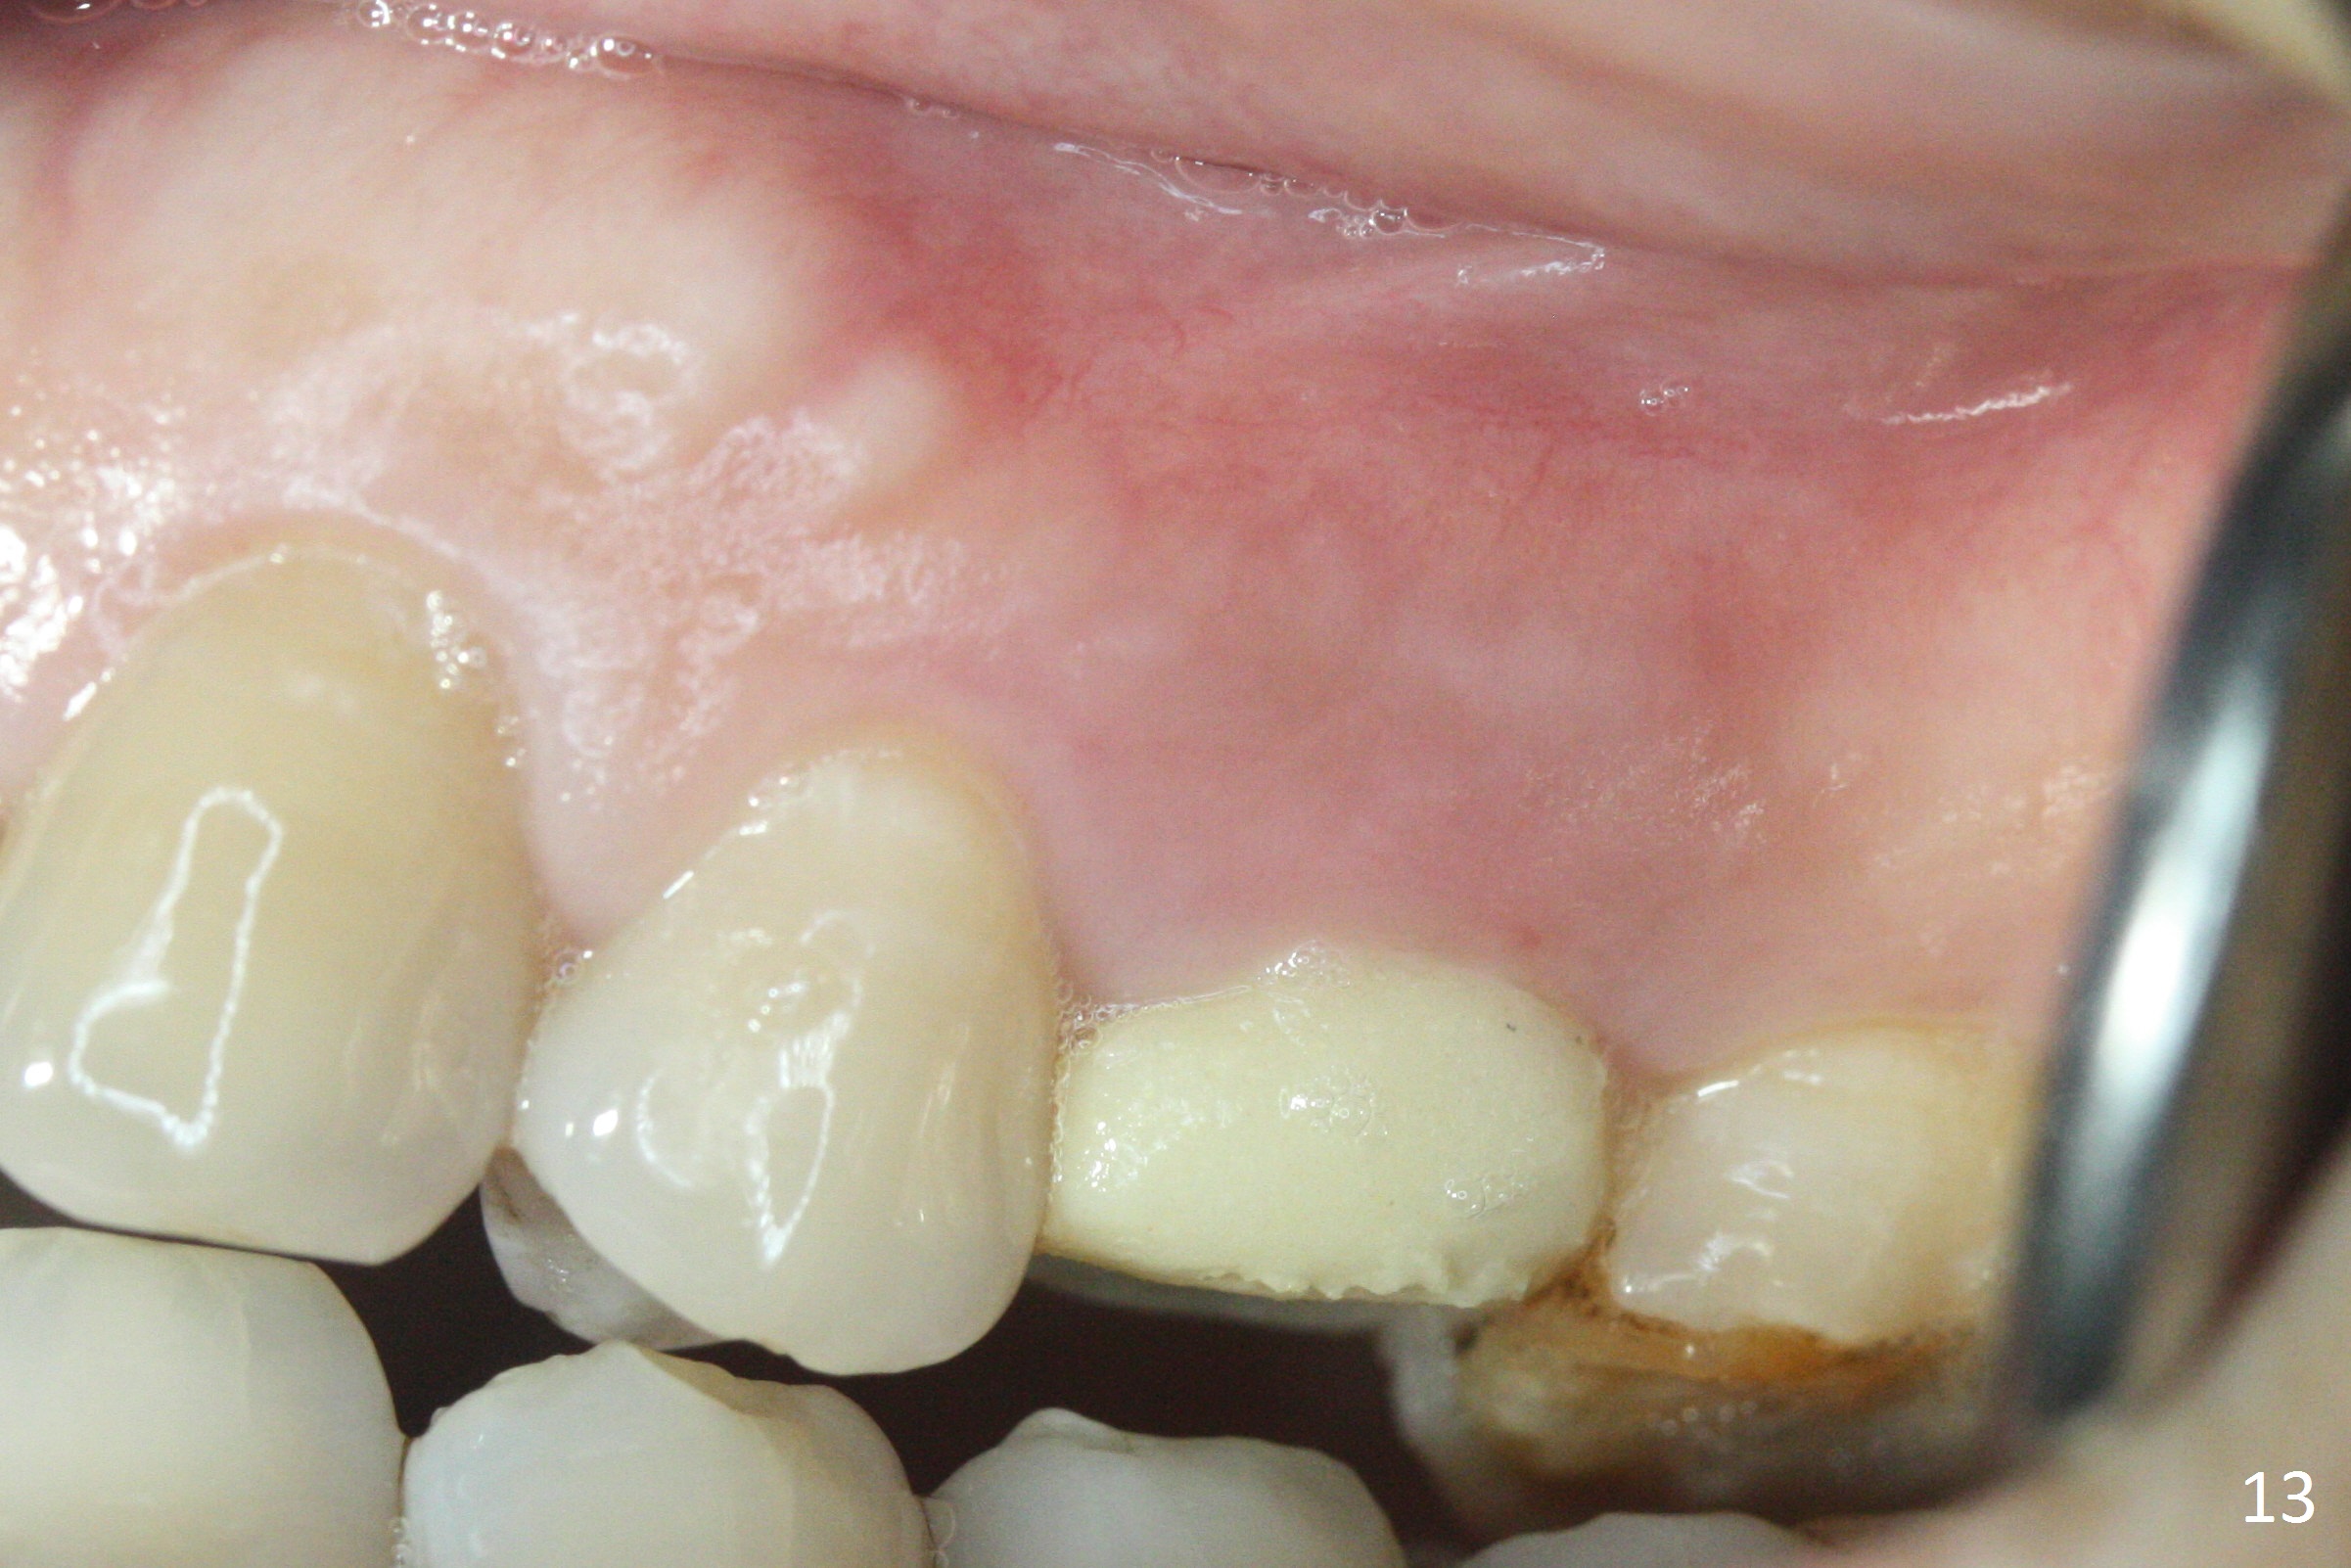

The buccal gingiva over the tooth #13 (Fig.1 white *) with crack (Fig.2 (mesial view of the extracted tooth)) is erythematous with deep buccal (B) pockets, which do not appear to extend the level of exostosis of the neighboring teeth (Fig.1 black *), i.e., coronal to the apical end of the crack with granulation tissue (Fig.2 *). Osteotomy is initiated with a 1.6 mm drill in the palatal aspect of the socket (Fig.3) so that an implant will be placed palatal (Fig.8,11) and there is enough buccal gap for bone graft (Fig.8 *). After withdrawal of 3.3 mm Magic Drill (trephine bur), the osteotomy (Fig.4 O) plug (red outline) is intentionally left in situ. When a 4x11 mm dummy implant is placed (Fig.5 (green outline), 6), the plug is compressed (Fig.5). With placement of a definitive implant (4.5x13 mm, Fig.7 (green), 9), the plug as well as the sinus floor (Fig.4 SF) is lifted (Fig.7 red curved line), 9 (arrowheads)). In brief the autogenous bone is used for sinus lift. There is no intra- or post-op nasal hemorrhage. With a small piece of gauze (Fig.8 G) in the implant well, allograft is placed in the buccal (mainly) and palatal gaps until the level of the implant plateau. Then a 4.5x4(3) mm abutment is placed (Fig.9-10 A). Next another piece of gauze is placed in the space corresponding to the abutment cuff (Fig.11 G) for fabrication of an immediate provisional (Fig.12 P). More bone graft is placed in the soft tissue zone (dual zone technique) after gauze removal and before provisional seating. With dual zone bone graft technique and provisional support, the soft tissue atrophy should be expected to be minimal (Fig.12 *). The zone of exostosis (more coronal) should be much less, since the bone density in the zone is high.

The buccal gingival inflammation subsides 1 week postop (Fig.13,14). There is no bone loss 4 months postop (Fig.15,16). The crown is recemented 6 months post cementation (probably due to short abutment); there is a residual cement (Fig.17 <), which is removed (Fig.18).